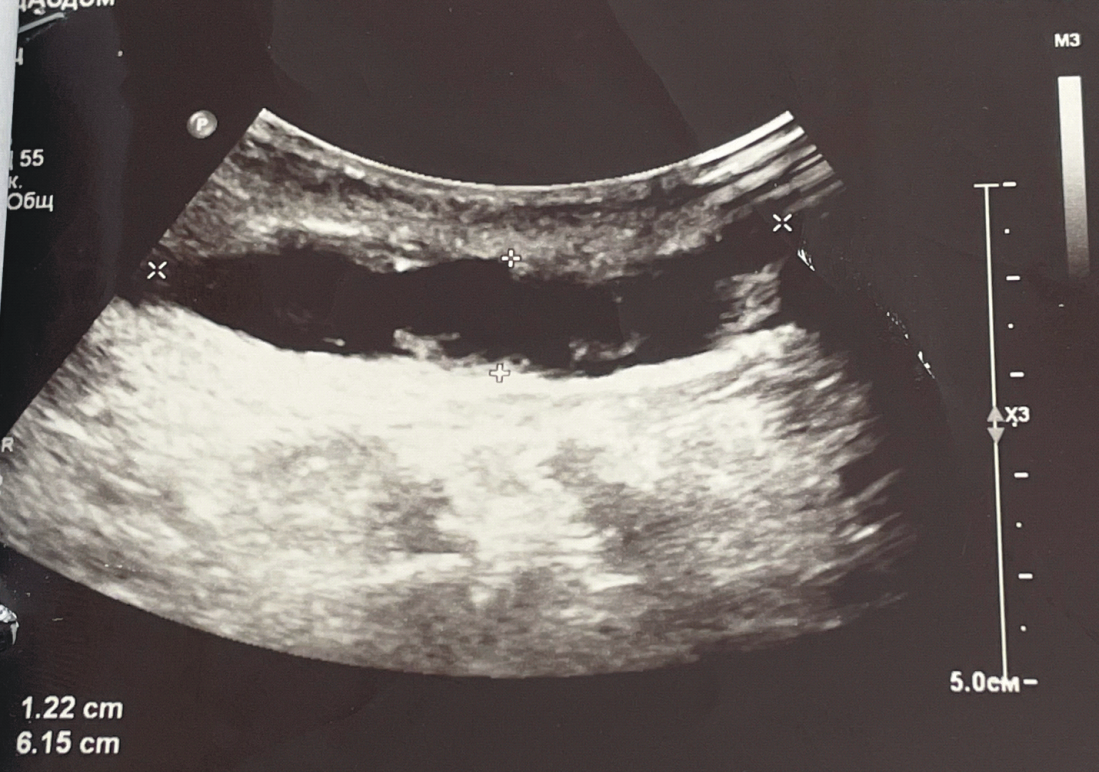

При заживлении нижнего угла раны отмечалось скопление жидкости в области оперативного доступа с образованием слюномы и постепенным сдавлением дыхательных путей, что приводило к нарастанию одышки у пациентки (рис. 3). Вследствие этого было принято решение поддерживать открытым нижний угол раны и обеспечивать отток слюны. Дренаж не устанавливали, чтобы снизить вероятность инфицирования раны.

Рис. 3. УЗИ мягких тканей шеи. Визуализируется слюнома размерами 6112 мм